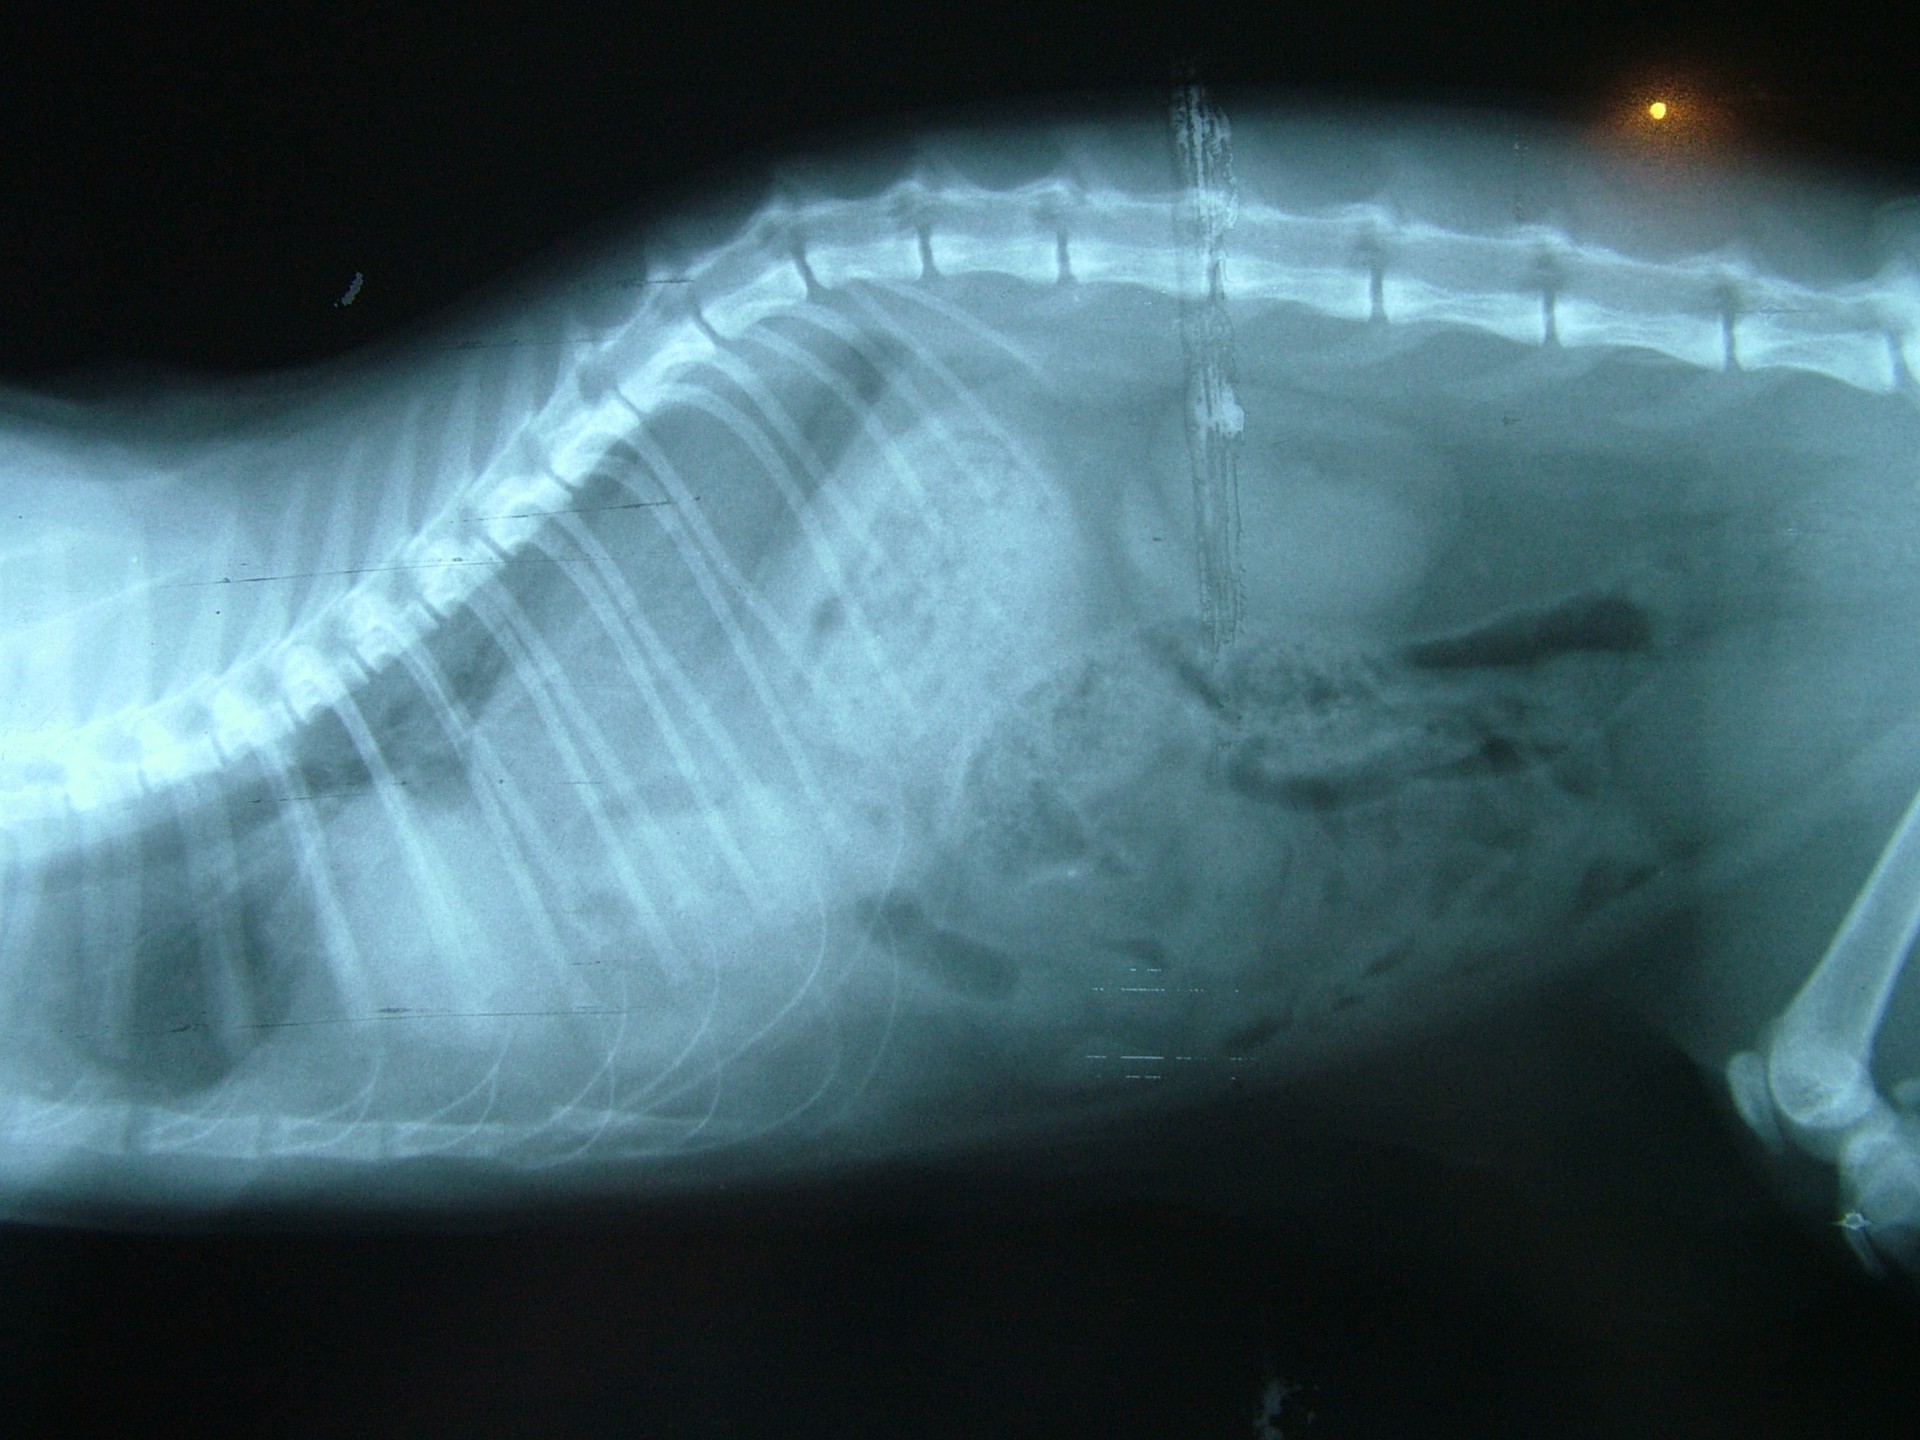

• A traumás eredetű rekeszsérv (hernia diaphragmatica traumatica) minden esetben valamilyen sérülést követően alakul ki. A rekesz folytonossága a sérülés következtében megszakad és az így kialakult sérvkapun keresztül a hasüregi szervek a mellüregbe előesnek. A betegség kórjóslata a trauma következtében kialakuló egyéb szervi sérülések miatt (máj-, léprepedés, tüdőzúzódás stb.) kifejezetten rossz. Az esetek döntő többségében az állatok súlyos általános állapotban kerülnek a rendelőbe, a diagnózis felállítását és a vérkeringés stabilizálását követően a traumás eredetű rekeszsérv azonnali műtéti ellátást igényel.

Mindhárom rekeszsérv forma meglehetősen ritkán fordul elő. A diagnózis felállítása a kórelőzmény, a klinikai tünetek a mellkas röntgenvizsgálata, a hasüreg ultrahangos vizsgálata alapján lehetséges.A rekeszsérv műtéti ellátása során a legnagyobb kihívást az jelenti, hogy a hasüreg megnyitását követően a sérvkapun keresztül levegő kerül a mellüregbe, ezáltal az állat spontán légzése leáll, így a műtét teljes ideje alatt asszisztált lélegeztetésre van szüksége.A műtét során a mellkasba előesett szerveket reponáljuk, a rekesz folytonosság hiányát megszüntetjük és a mellkasban lévő szabad levegőt eltávolítjuk, ezzel biztosítva az állat spontán légzését. A műtétet követő napokban legfontosabb feladat a vérkeringés és a légzés folyamatos, kórházi körülmények közötti kontrolálása.Az idejében felismert és megfelelően ellátott veleszületett rekeszsérv jó eséllyel gyógyítható, a traumás eredetű sérv ellátásának eredményességét általában az egyéb szervek sérülése határozza meg.